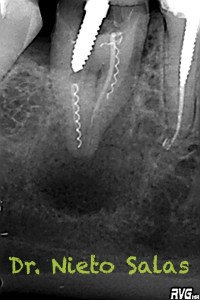

Nos remiten a la clínica a una paciente con un tratamiento previo de endodóncia realizado ya hace unos 5 años y que presenta una agudización del proceso. Se trata de un fracaso endodoncico por una falta de sellado tanto coronal como apical, en el que en el espacio intra-conductos nos encontramos dos léntulos, y en el acceso a los mismos un perno prefabricado.

Los puntos fuertes serán la retirado del perno y de los léntulos, a priori, no muy complicado, pero todo puede cambiar dentro de los conductos. Nuestro objetivo en la primera sesión será llegar a determinar la longitud de trabajo de los diferentes conductos, conformarlos y colocar nuestro Hidróxido de Calcio.

Dentro de los ultrasonidos, removí el perno con una ET20 de Satelec y ProUltra nº4 y ET25 para los léntulos.

Presentaba un sistema de conductos en el que el conducto distal era acintado y los mesiales podían unirse después de instrumentarlos.